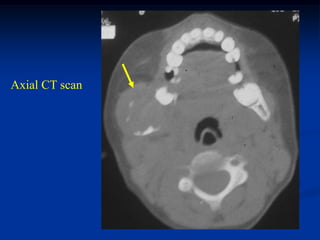

Case #429.2

EG pelvis

39 year male with dull aching pain left hip for 9 mos.

Axial CT scan

Cor and Sag CT